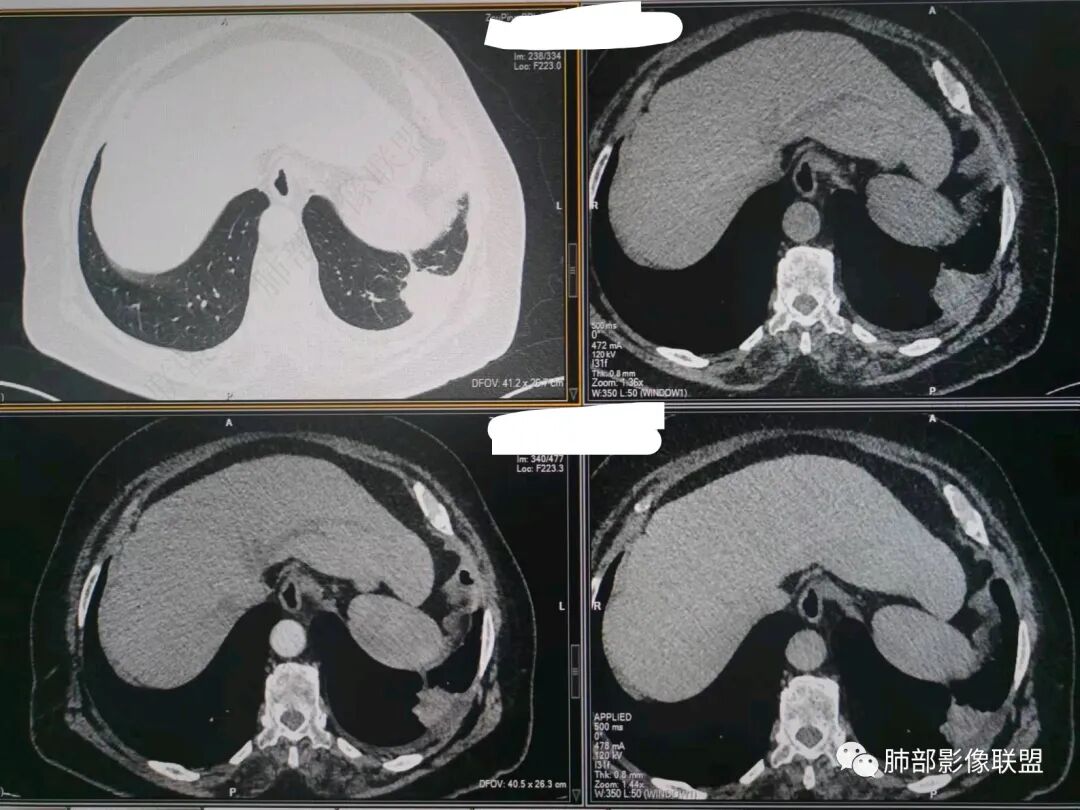

看看这个,骨头都侵袭了。

今天的病例有些伪影。

看起来就觉得放射状伪影。

我就不知道这些是胸水,伪影导致密度增高?还是胸膜增厚?

我只是邓较瘦:今天平扫的像栽赃, 增强感觉是增厚的胸膜。

而且旁边这么宽的少,所以觉得很奇怪,不太符合,我是怀疑与照片有关。

你对比一下两侧的密度。肌肉密度不一样。